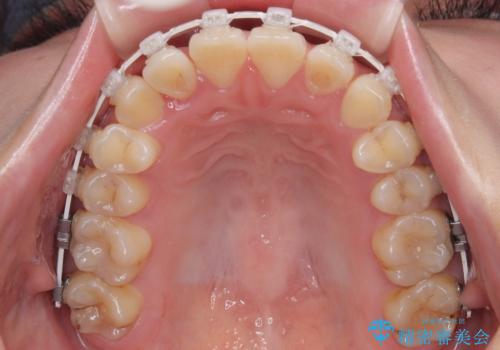

- 審美装置

- 上下前歯のデコボコを気にして来院された患者様です。

ワイヤー矯正でもマウスピース矯正でも可能でしたが、短期間で、自身の手を煩わせることなく治療を行いたいとのことで、ワイヤー装置にて矯正治療を行うこととしました。

僅か8ヶ月という短期間で、綺麗な歯列に仕上がりました。